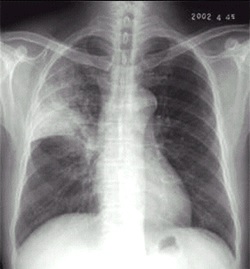

02卷-4.男性,24歲,發(fā)熱、咳嗽、咳痰4天。診斷(本題滿分2.00分)

A.右上肺不張

B.右上胸膜肥厚

C.右上肺癌

D.右上肺炎

本題答案:D

題目解析:【該題針對(duì)“X線-肺炎”知識(shí)點(diǎn)進(jìn)行考核】